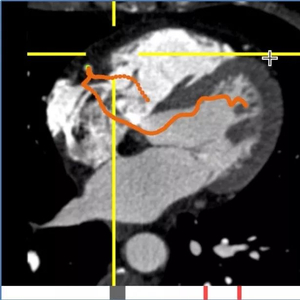

看看下面这张图:阿里AI在0.5秒内全自动提取的单根心脏冠脉,医生可从重建的影像上快速发现病灶。右上为血管上的软斑块,右下为钙化斑块。